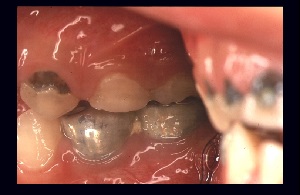

もし、この状態で単に治療だけを繰り返していたら、将来どのような状態になるだろう?

きっと小学校へ入学する頃、乳歯は残根になるだろう。

(図6)

第1大臼歯は、まだ健全なので乳臼歯の抜歯で処置終了とする。

しかし次に、上顎永久前歯が萌出するとこのような状態になるに違いない。

単にう蝕処置の繰り返しのみでは、健全な永久歯の獲得にはつながらないことを伝える。

言い換えれば、処置法のみを教授する教育では、根本的な解決にならないことがわかる。